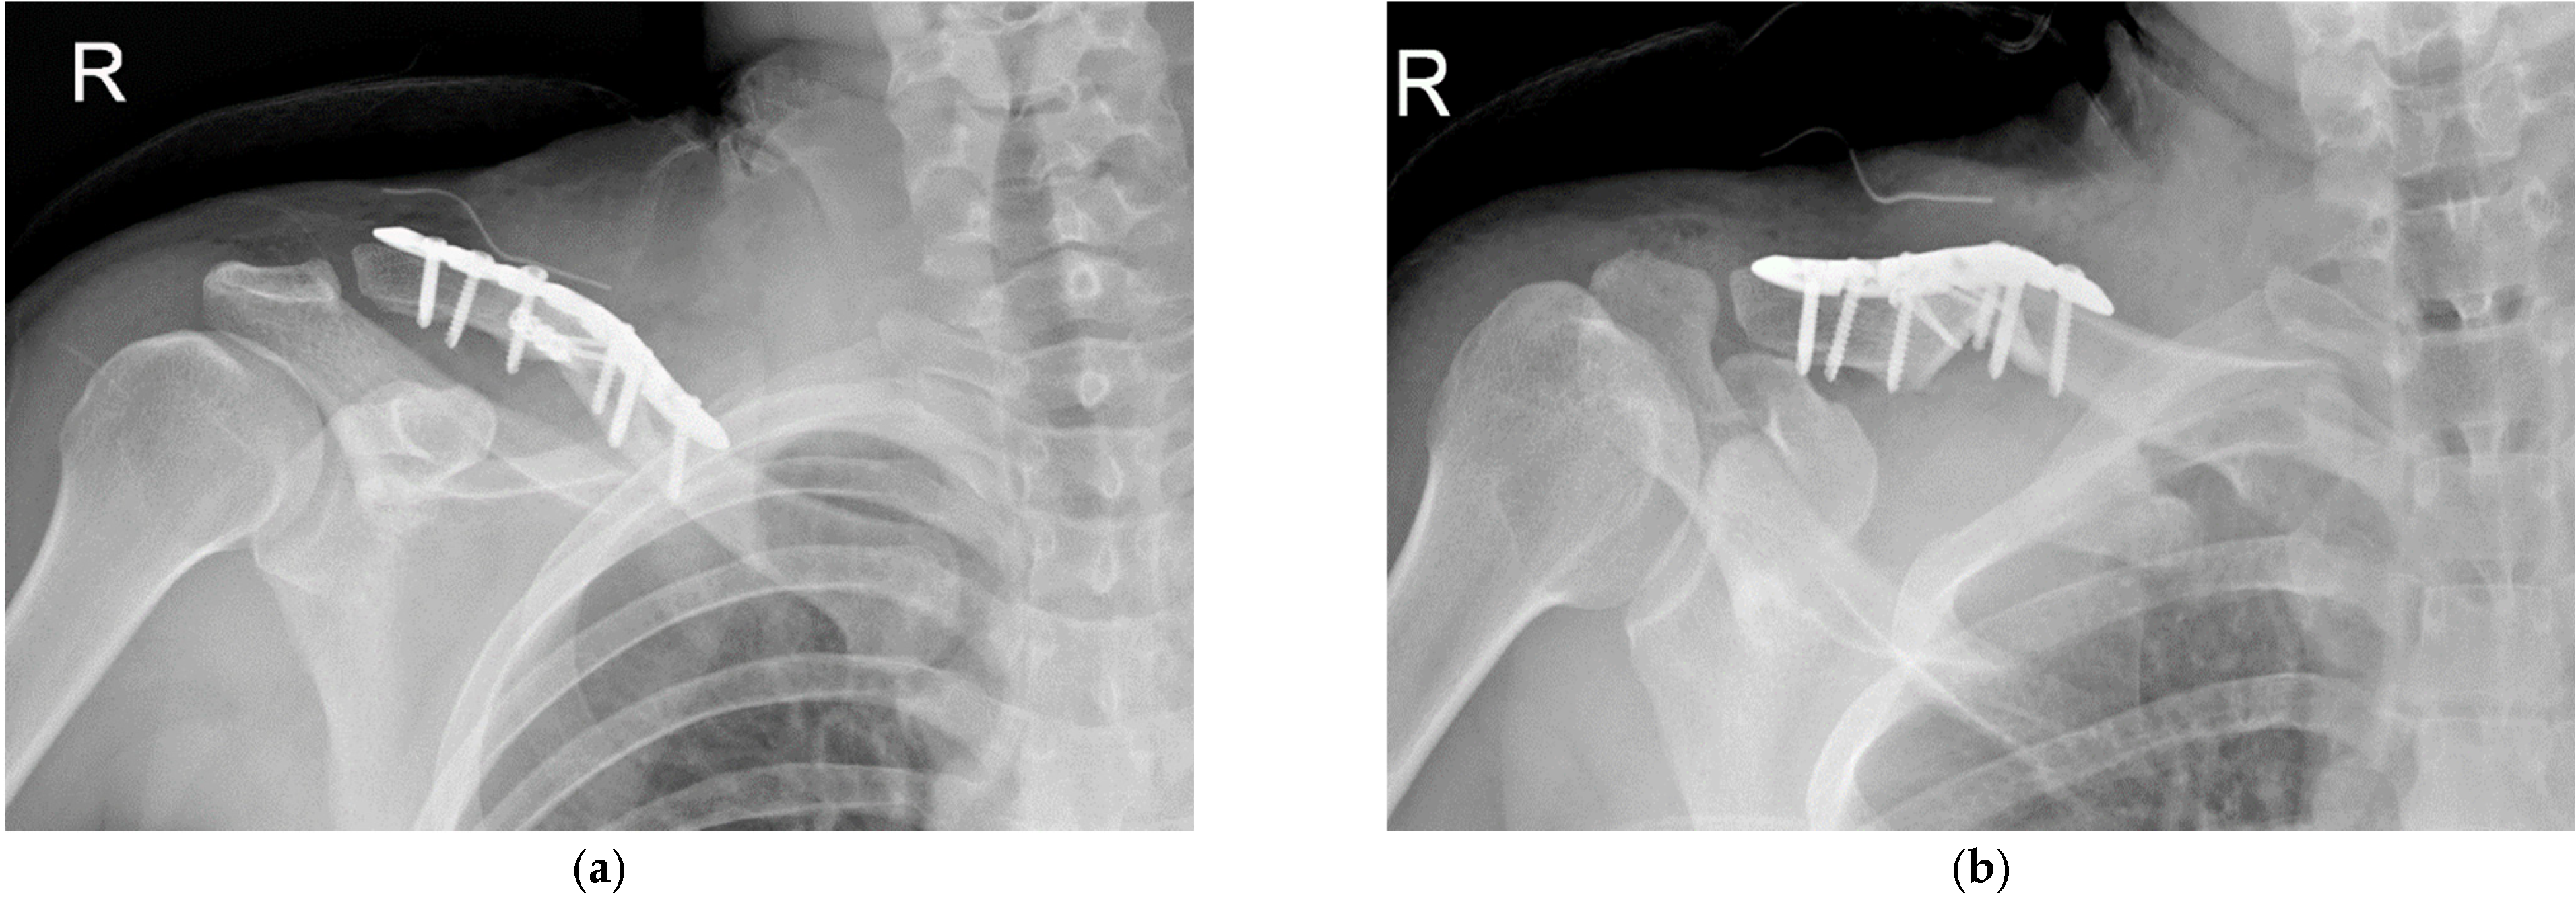

Intuitive and Minimally Invasive Surgical Technique for Comminuted Mid-Shaft Clavicle Fractures: Fixation with an Anterior Mini Plate and Superior Locking Compression Plate

2. Materials and Method

3. Results